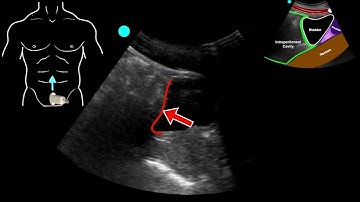

PoCUS Lung - Pneumothorax/Lung Point